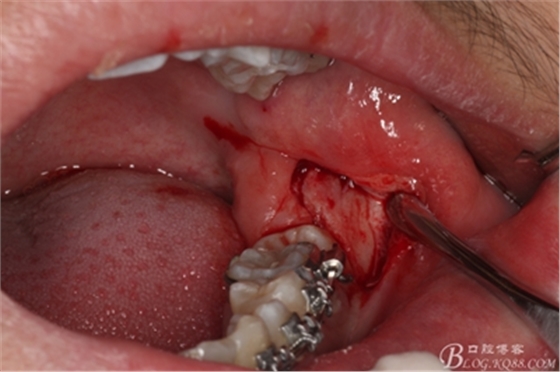

圖9.高速拔牙手機(jī)去骨

圖10.去骨后暴露出38的牙冠